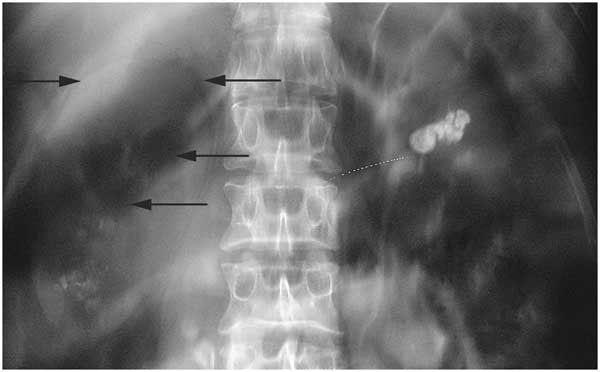

• 신장결석: 갑작스럽고 매우 강한 통증, 등에서 옆구리로 방사

• 신우신염: 고열, 오한, 배뇨 통증과 함께 옆구리 통증 발생

• 신장결석 통증은 어떤 특징이 있나요?

• 갑작스럽고 매우 강한 통증이 특징이며, 등에서 옆구리로 퍼지는 양상이 많습니다.